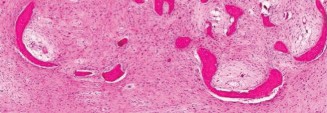

The biopsy of this lesion is shown inFigure 8–41. What of the following histologic features is characteristic of this lesion? 1. “Alphabet soup” pattern of bony trabeculae

Figure 8–41

The correct answer is (A). Histologically, fibrous dysplasia appears as poorly mineralized immature fibrous tissue surrounding islands of irregular trabeculae of woven bone, termed “Chinese letters” or “alphabet soup.” These lesions can be associated with secondary aneurysmal bone cysts, so sometimes cavernous blood-filled spaces are seen on histology, but this is not a characteristic feature and cannot be used alone to make the diagnosis.